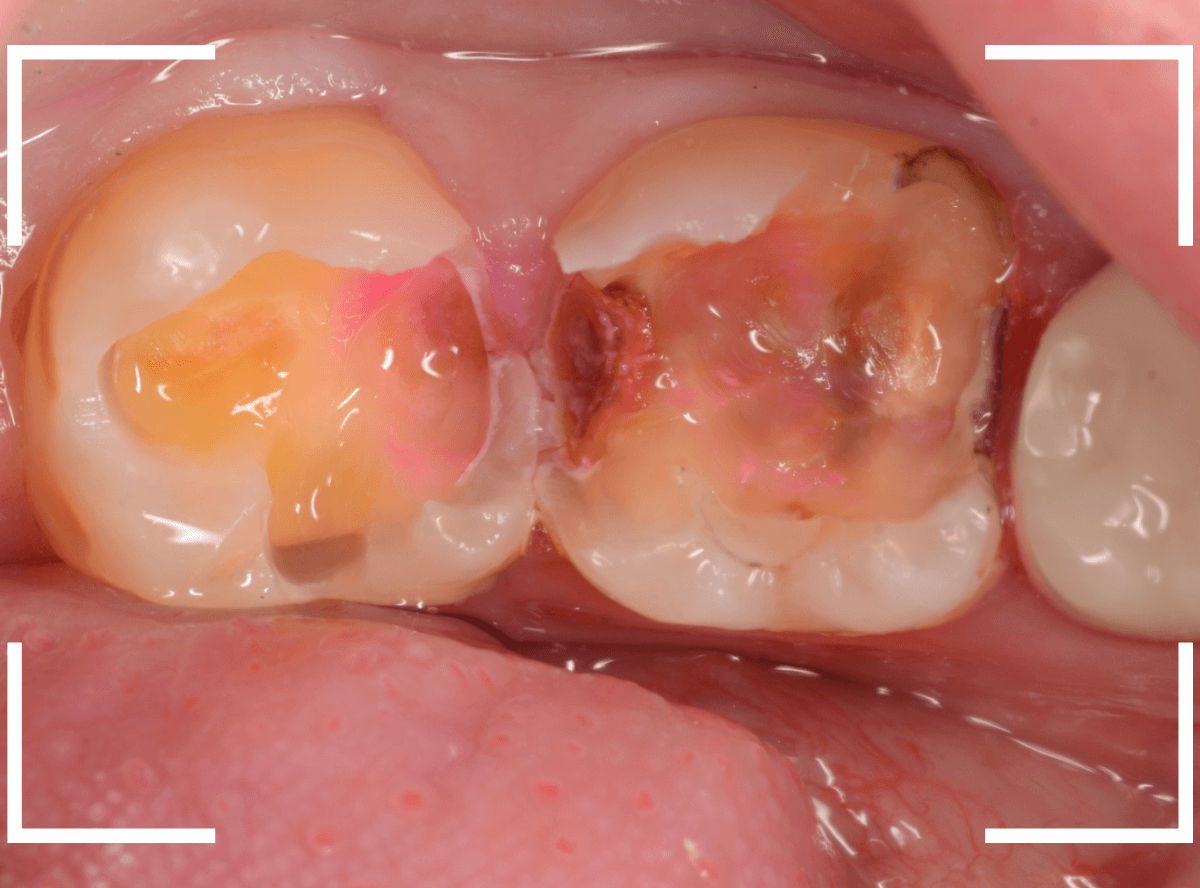

Case.21 神経に達しそうな2本の大きな虫歯

上の小臼歯の側面が明らかに虫歯になっている患者さんです。

患者さんは特に症状を感じてなさそうですが、恐らくは中で大きな虫歯になっているでしょう。

2本とも、神経に達してしまいそうな大きな虫歯であると思われます。

まず、奥の歯のつめものを外してから、虫歯の治療を開始します。

手前の歯が大きな虫歯が見えてきました。

神経に達してしまいそうな虫歯ですので、ある程度削ったところで、少しずつエキスカという道具で掻き出すようにして、虫歯を除去します。

虫歯は歯を溶かして進行しますので、骨よりも固い歯もちょっと掻き出すとボロボロと崩れるようになってしまっています。

かなり虫歯を除去したところで、手前の歯は神経が顔を出してしまいました(露髄といいます)。

神経を除去する治療が必要かもしれないです。

全ての虫歯を除去したところです。

幸い、後ろの歯は薄皮一枚のところで神経まで達していない虫歯ですんでいましたが、大きな虫歯だった事には変わりありません。

いつものように、神経が痛み出さないように祈りつつ、お薬で保護して経過観察します。